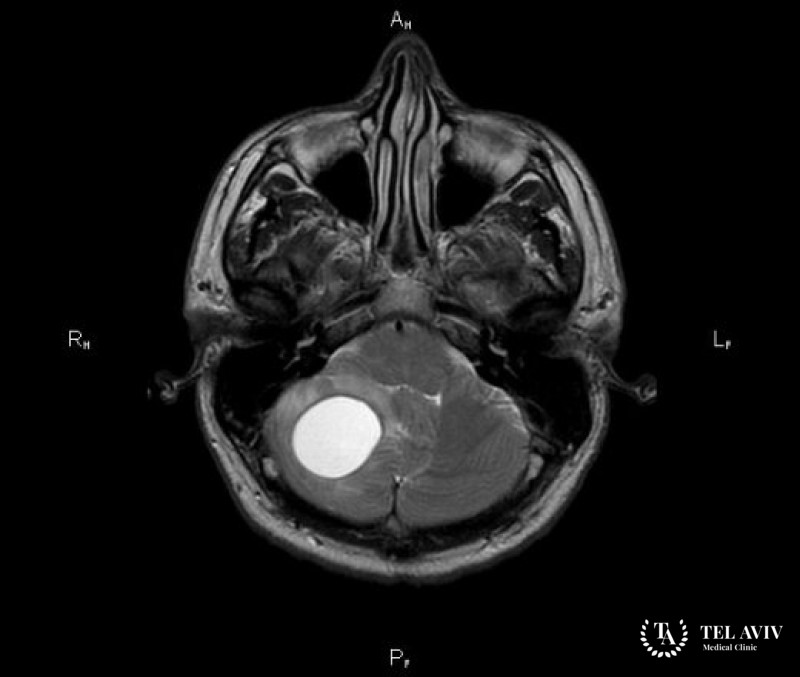

Гемангиобластома головного мозга – это развивающаяся из кровеносных сосудов доброкачественная опухоль, которая зачастую локализуется в мозжечке. К основным факторам, повышающим […]